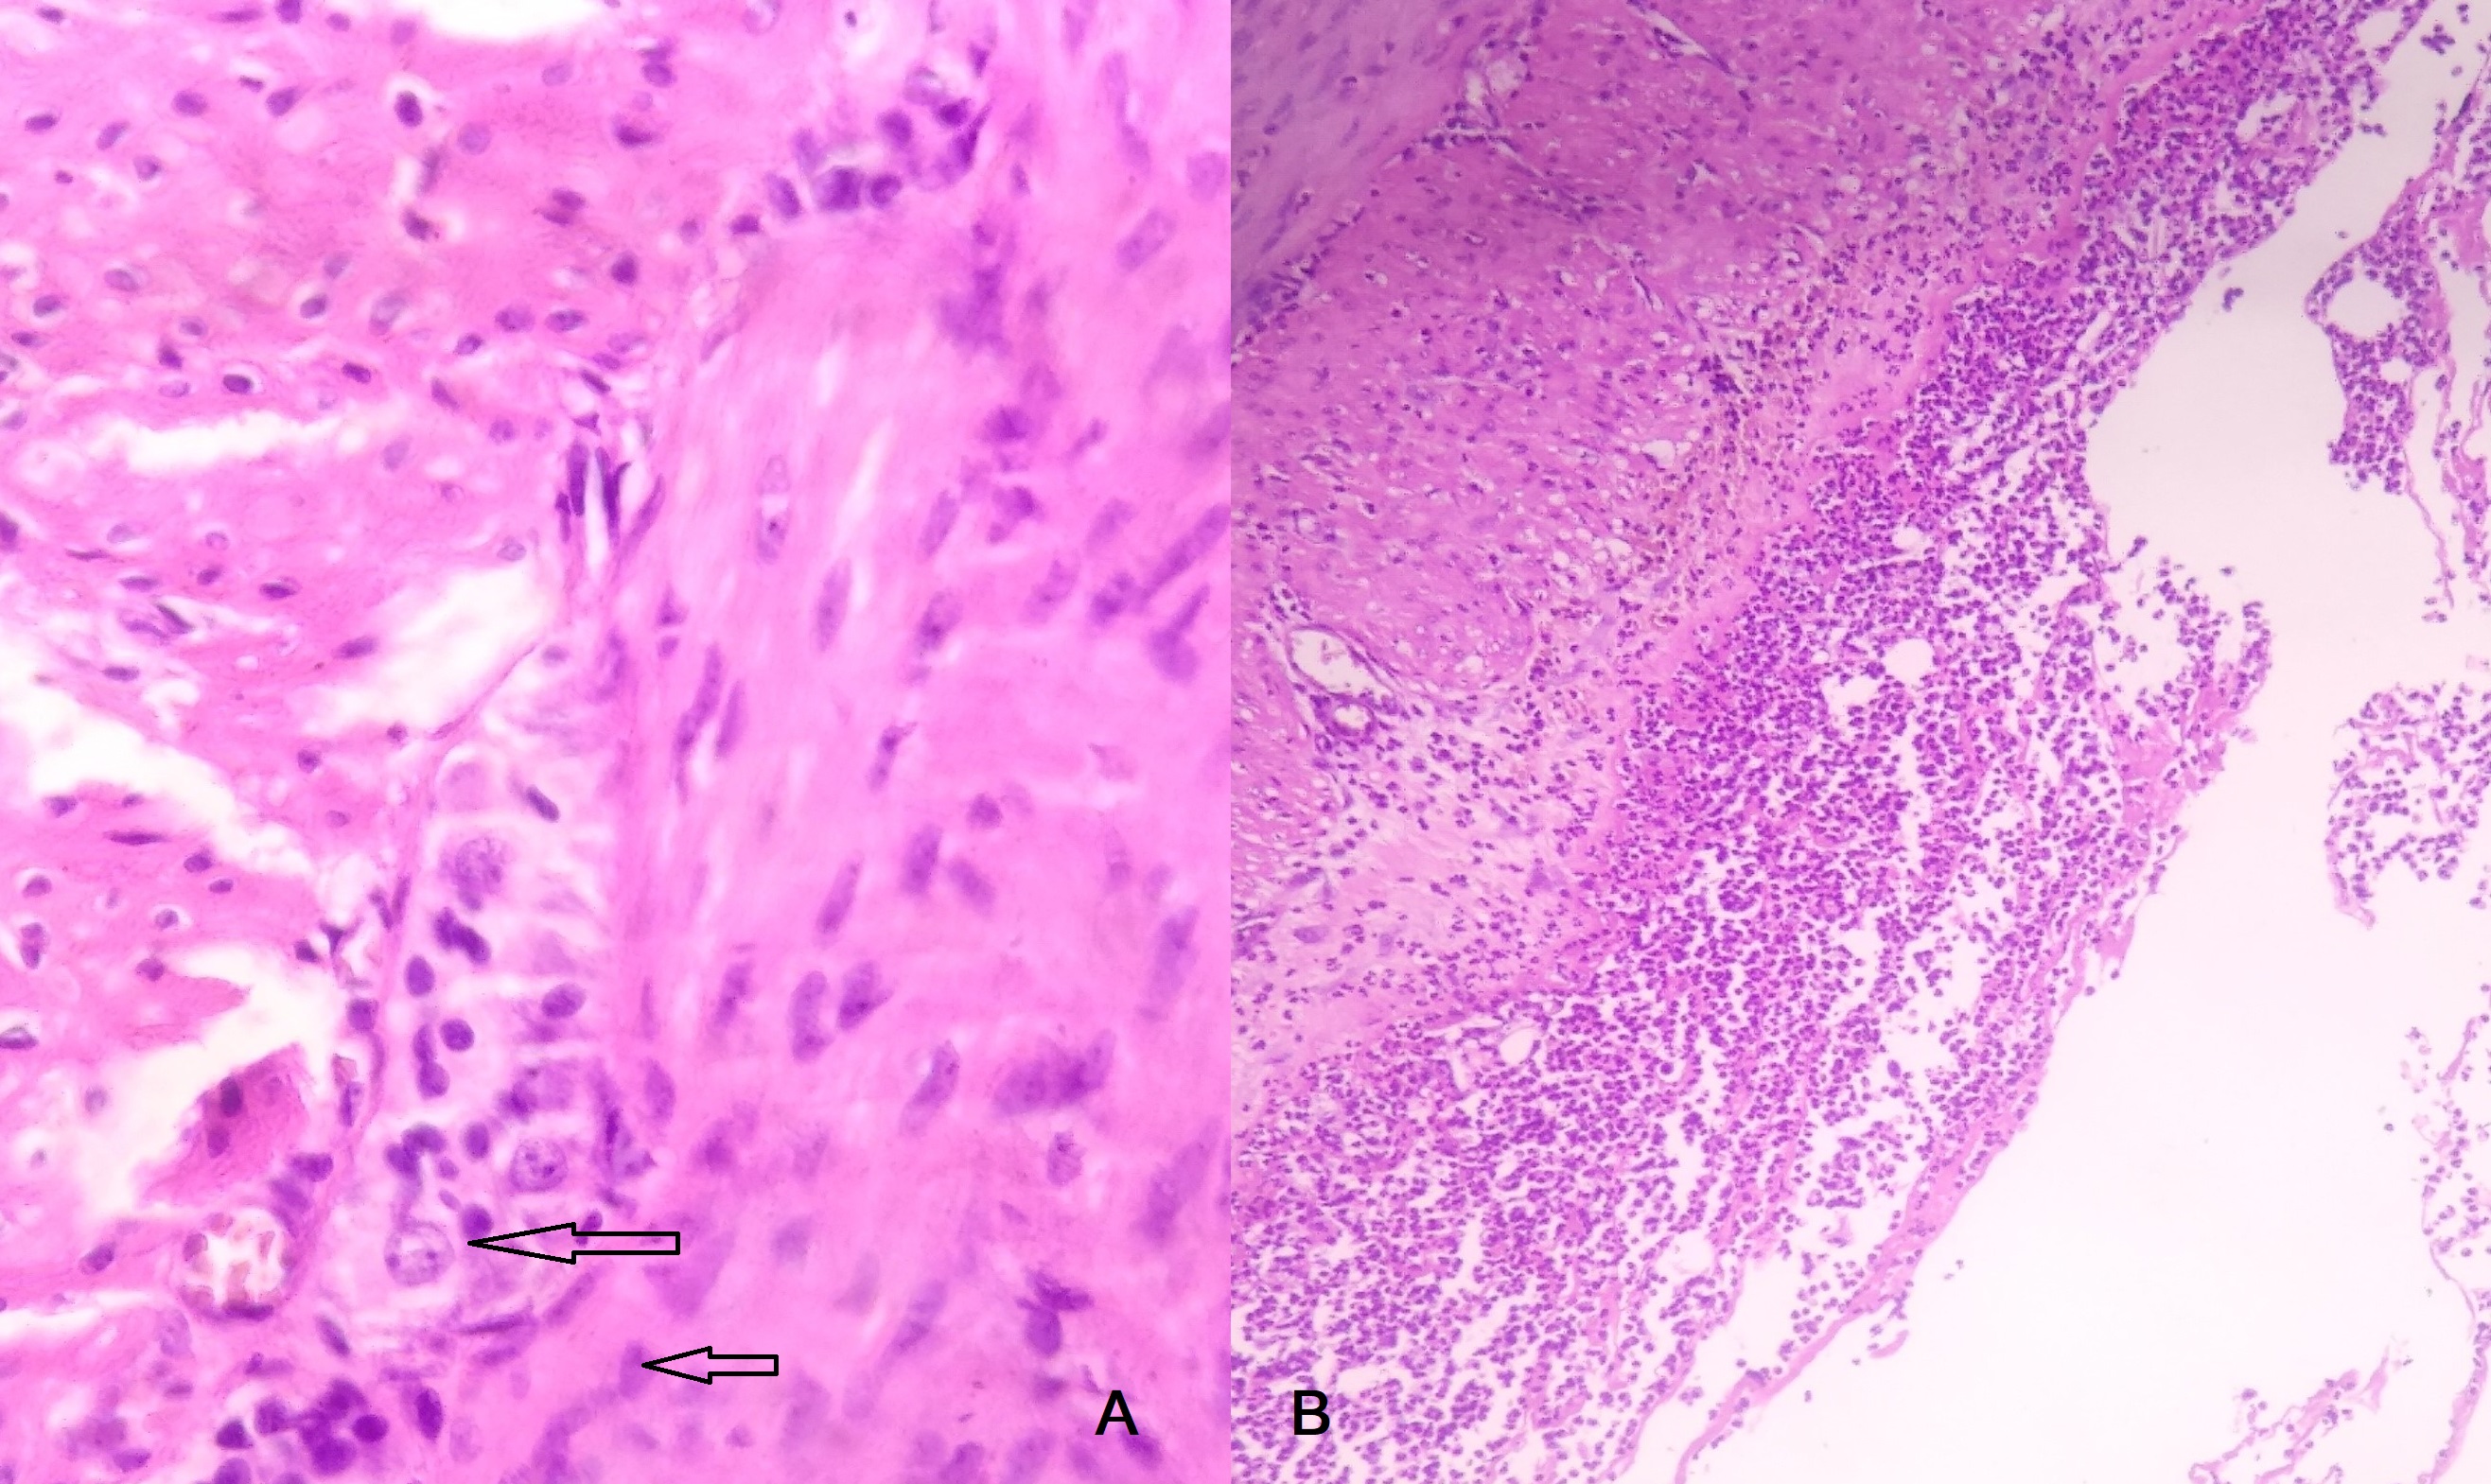

Post-operatively, abdominal distension and bilious vomiting persisted.Histopathological examination of all specimens revealed immature ganglion cells with no hypertrophic nerve bundles(Fig. 3a). Conservative treatment like frequent rectal wash, NG drainage, I/V fluids and prokinetics failed to improve his condition. Therefore, re-laparotomy was performed at 9 days of life. Operative findings were similar to previous laparotomy findings. Resection of the isolated jejunal segment with end to end jejuno-ileal anastomosis and loop ileostomy were performed. Post-operative period was uneventful and patient was discharged on 6th post-operative day. Histopathological examination of the resected dilated jejunal segment showed normal morphology with mature ganglion cells, subserosal neutrophilic suppuration was presentwhile muscularis propria and mucosa were normal (Fig. 3b). Immunohistochemistry was not performed due to financial constraint. Patient is now 1 month old and awaiting ileostomy closure.

Fig.3

A) Mature as well as immature ganglion cells (arrow) are seen in the muscularis propria of ileum H & E stain. Original magnification X400; B) Prominent neutrophilic infiltration with suppuration is noted within the serosa of ileum. H & E stain. Original magnification X100.